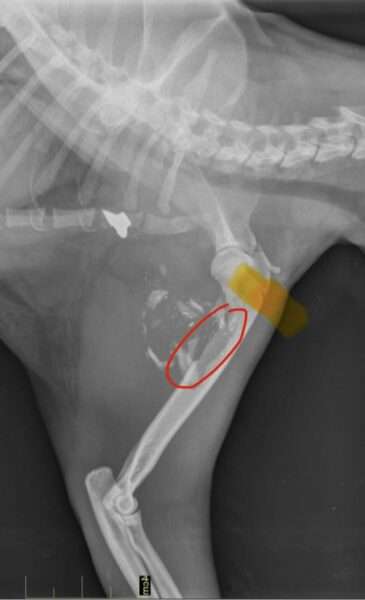

📸 Résultats de la radio : une consolidation imparfaite

La radio de contrôle montre une évolution contrastée :

🔴 Une partie de l’os a commencé à se consolider

🟡 Une autre partie s’est écartée et se consolide de travers

La vétérinaire recommande la pose d’une plaque, une intervention qui devra être confirmée par un vétérinaire spécialiste.

👉 Une opération sera quoi qu’il arrive nécessaire, dès la fin de tous les traitements en cours.

Radio Balthazar